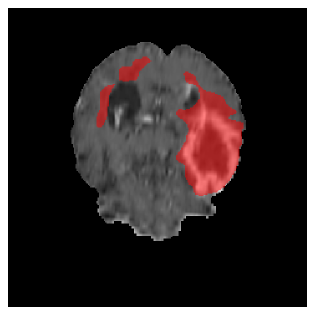

Appendix A Qualitative results

Figure 5 illustrates the segmentation evolution for the same BRATS patient in S2 sequence. The key difference here is that the best buffer-free strategy is EWC (=1), and training on BRATS data starts from episode 2 instead of episode 1 as BRATS is encountered at episode 2 in S2. The cumulative approach retains segmentation across episodes but continues to generate false positives, which become even more pronounced in the final episode. The naive approach, lacking a CL mechanisms, completely overrides previous knowledge, leading to failed segmentation in later episodes. EWC (=1) approach initially maintains segmentation but experiences a sharp decline in episode 4, where it fails to segment the tumor. In the final episode, it undersegments the lesion, missing a significant portion of the tumor. In contrast, the proposed approach consistently preserves segmentation across episodes. While initially introducing false positives, it gradually refines predictions, retaining the tumor region while minimizing misclassifications. It maintains clear tumor delineation by the final episode, demonstrating effective knowledge retention and adaptability throughout training.